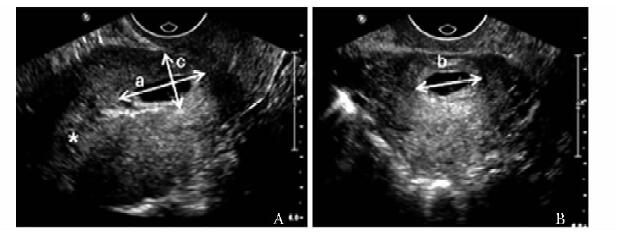

方法  收集2011年11月至2013年1月北京协和医院临床确诊为剖宫产切口瘢痕妊娠、并接受手术治疗的35例患者, 术前进行二维及三维超声检查, 获得病灶最大径、病灶平均径、病灶植入瘢痕面积、植入体积及植入深度; 按有无胎心搏动、病灶类型、彩色多普勒血流分级及术前有/无甲氨蝶呤联合治疗进行分组。记录患者手术中出血量, 分析超声参数与出血量的相关性, 比较组间出血量差异; 将病灶按出血量进行分组, ≥ 200 ml组和 < 200 ml组, 应用Logistic回归分析影响出血量的独立危险因素。

Methods  A total of 35 CSP patients who received operational treatment from November 2011 to January 2013 were enrolled in this study. The 2-and 3-dimensional ultrasound examinations were performed before the surgery, and the following parameters were recorded:maximum diameter of lesion(Dmax), average diameter of lesion(Dmean), implantation area of lesion(S), implantation volume of lesion(V), and implantation depth of lesion(Dimp). All these cases were divided into different groups according to the following characteristics separately:with/without fetal heart beat, lesion shown as gestational sac/mass, vasculature grade poor/median/rich, whetheror not combined with methotrexate(MTX) treatment prior to operations. The amount of bleeding during the operation was recorded. The correlation between the above parameters and the amount of intraoperative bleeding was analyzed. The bleeding amount of different groups was compared. Also, the patients were divided into two groups according to bleeding amount ≥ 200 ml and < 200 ml, and the potential independent risk factors of bleeding were analyzed using Logistic regression.